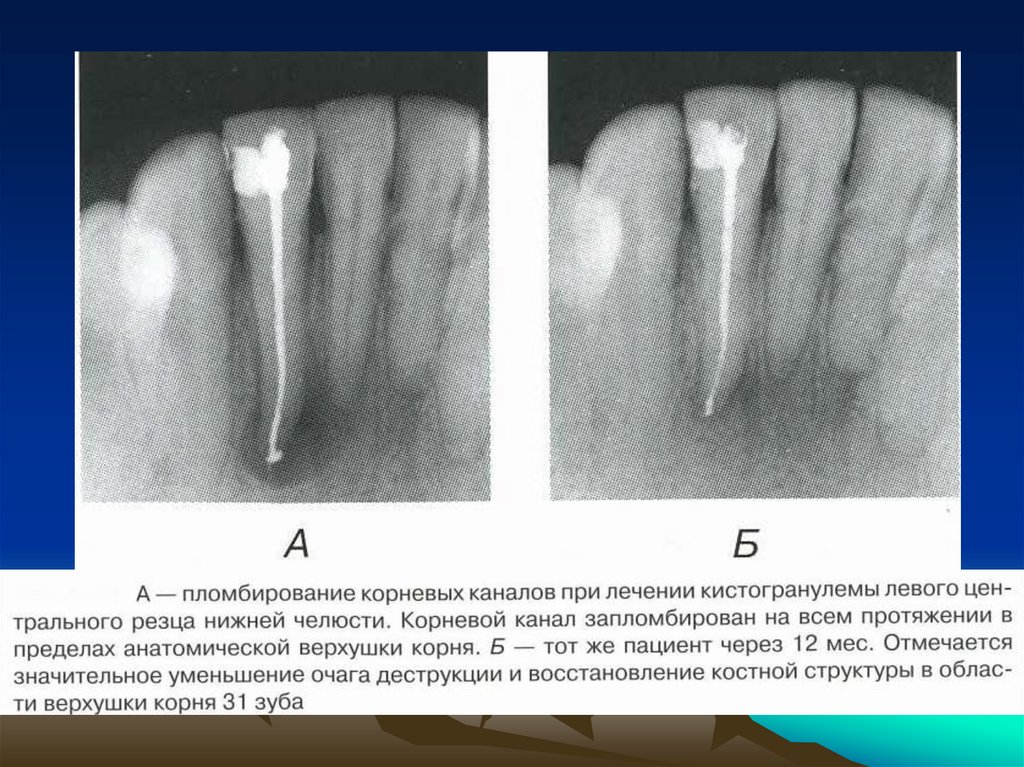

соматического

и